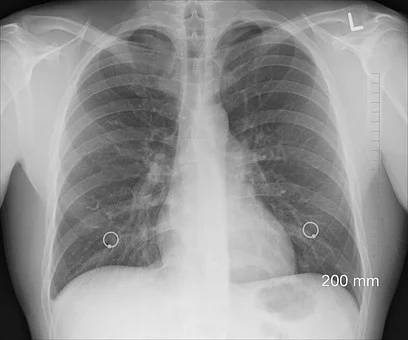

폐에 발성하는 악성 종양인 폐암은 늦게 발견할 경우 이미 다른 장기에까지 암세포가 퍼지면서 생명이 위험한 상태가 됩니다. 따라서 평소 폐암 초기증상을 인지하고 미리 진단하여 조기 치료를 하도록 노력해야 합니다. 오늘은 단계별 폐암초기 증상에 대해 살펴보겠습니다.

폐암 초기증상 8가지